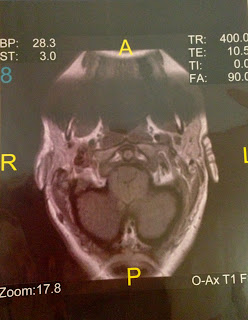

(fig 1.)

This is my actual MRI from 10-24-2005, showing the massive herniation all the was to C-2. along with a brain stem hump that I still have. (looking as if I were sliced in half top to bottom through the nose to the chin)

This is another of my MRI's 10-24-2005 pre-surgery. (this is looking as if cut in half ear to ear looking down through my neck)

My brain was so herniated that it was crushing everything in its way, as you can tell by fig. 2. Look in the center of this picture and at the section that looks like 3 circles together the top one, that is the that your brain stem meets the spinal cord in your foramen magnum. The spinal cord is supposed to be free floating in CSF (cerebral spinal fluid). It is also supposed to have plenty of room (extra) for all of your accessory nerves, etc. Foramen magnum is Latin and means, "great hole", oh heck, not in my case.

My herniation was 25mm below the base of my skull on one side and about 19mm on the other side by the time I had brain surgery which was November 18, 2005. I had been having sever migraines since I had a car accident back in 1987. This was the trigger point of my growth. In some cases this happens but it is more common it is a hereditary trait. In my case I had no blood flow out of the 4th ventricle of my brain, which kept pounding inside my head and on my pituitary gland which in turn messed up my endocrine system which them made my thyroid gland not work correctly. That made me gain weight over time. I was nearly 200 pounds. I felt like crap daily! (still do a lot) I'm talking migraines, migraines and more migraines! I had/have numbness, confusion, memory loss, spots in my eyes, body drops, sleeplessness, then over sleeping, pins and needles, burning sensation, superficial thrombophlebitis, a brain stem hump from c1-c2, scoliosis, occult tethered cord, fibromyalgia, chronic fatigue syndrome the list goes on. I will go into detail later. Here is a picture taken the day after I came home from surgery. The day before Thanksgiving. I can remember my brother calling me zipper-head because of the 43 staples I had for the 11 inch opening they had for the the posterior fossa decompression.

This MRI was post surgery and as you can see the great area there that I no longer have the herniation there, but the brain stem hump still exists. This is permanent damage and irreversible. You can't see it the greatest, but if you look really good you can just make out the titanium plate at the end of my skull line, well I have to hold my brains in some how, lol.